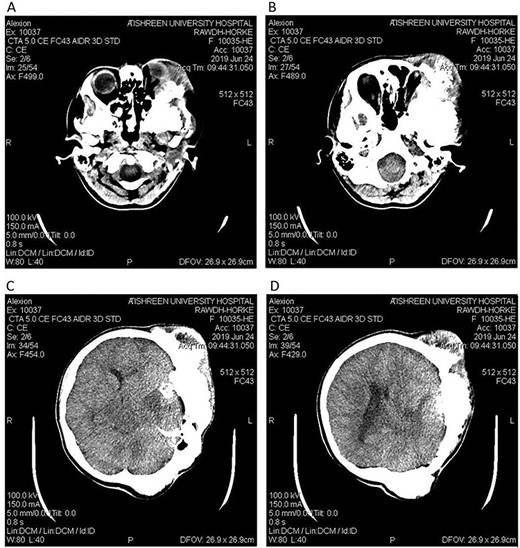

CT head bone window (A–C). A. Invasion of the frontal bone. B. Invasion of the orbit. C. Invasion of the parietal bone. D. Invasion of the sphenoid, temporal and parietal bones.

A 17-year-old female presented with a history of osteosarcoma that was confirmed after undergoing a surgery to remove an enlarging bone tumor in the left temporal region 2 years ago. She later got pregnant and delivered her child but never got back for a checkup until she was admitted to our hospital with a severe and unresponsive to medication headache that progressed over the course of 6 months and blurred vision that progressed to complete left-sided vision loss. Physical examination revealed a tough and mobile yet fixed at the base 7-cm mass towards the left of the frontal bone. Many more masses were revealed in the left side of the skull including the anterior cranial fossa, orbit, base of the skull and the left part of the occipital region where the previous procedure was performed (Fig. 1). These masses had been increasing in size probably under the influence of pregnancy hormones causing pain that radiated along the orbital and maxillary branches of the left trigeminal nerve. Physical examination and past medical history were otherwise unremarkable. Laboratory tests were all normal, and her family history was negative. Staging studies showed no evidence of distant metastatic disease in the chest, the abdomen and the pelvis. CT scan of the skull revealed a bone-forming non-lytic lesion accompanied by periosteal reaction. This lesion bulges to the outside towards the scalp spreading into both the soft tissues and the inside of the entire left side of the skull with a sunburst-pattern (Figs 2 and 3). Its rims are unsymmetrical and pointy, and it bulges into the left orbit outside the muscles causing exophthalmos with a semi-complete proptosis of the eyeball out of the orbit (Figs 2 and 3). This lesion applies pressure to the left frontal and temporal lobes causing mild edema in both these lobes without invading the brain tissue. This edema in turn applies pressure to the left lateral ventricles (minor shift of the elements of the midline to the right side can be seen on CT) (Fig. 4). Due to the tumor’s wide spread, the surgical procedure was performed in two stages (approximately 6-hour-long each). In the first stage, the bone mass was removed through a procedure of wide skull approach including the frontal, temporal and parietal bones and a removal of the invading part of the temporal muscle. Moreover, the lateral wall and roof of the left orbit were removed, the left optic nerve was dissected free and part of the meninges was removed and replaced with an autogenic patch from the fascia lata. Then, the bone loss was compensated for by using bone cement Synicem VTP (poly methyl methacrylate and Barium sulfate), and the orbit was rebuilt; the eyeball was placed back with noticeable decline of the exophthalmos. In the second stage, a complementary left parietal occipital incision of the previous approach was performed 3 weeks later; the remaining of the frontal and occipital bones was removed, and a partial mastoid surgery was done. Furthermore, the cavernous sinus were revealed and found to be not invaded. Later on, the normal skull shape was restored using the same cement. The histopathology of the lesion revealed proliferation of neoplastic chondroblasts, osteoblasts and spindle-shaped cells. The features are consistent with low-grade chondroblastic osteosarcoma (Fig. 5). The patient did not need ICU admission. She recovered well 3 days after the surgery and was discharged with no deficits. A CT scan that was performed post-operatively revealed that the masses were successfully excised (Figs 6 and 7). At the last follow-up 1 month post-operation, the patient was scheduled to undergo a course of radiotherapy, 60 Gy of radiotherapy in 30 fractions over 4 weeks without chemotherapy, as it is not recommended with low-grade osteosarcoma.